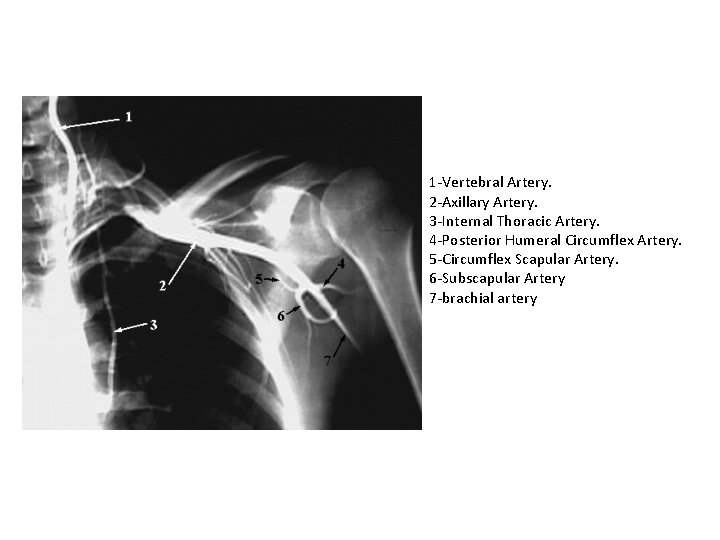

UPPER LIMB VESSELS

1 -Vertebral Artery. 2 -Axillary Artery. 3 -Internal Thoracic Artery. 4 -Posterior Humeral Circumflex Artery. 5 -Circumflex Scapular Artery. 6 -Subscapular Artery 7 -brachial artery